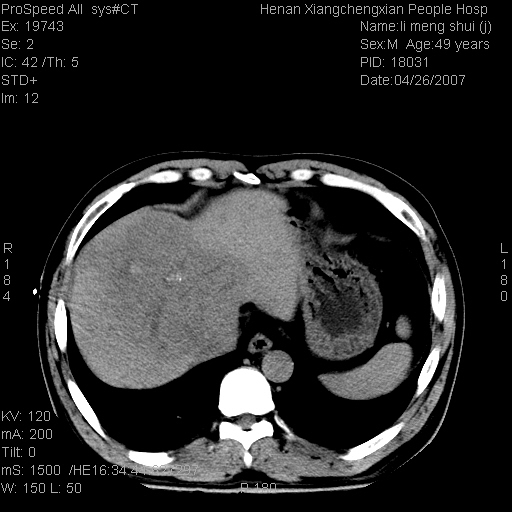

| 患者,男,49岁, 腹疼伴恶心\\呕吐20天,20天前无明显诱因出现右上腹部疼痛,钝疼,无放射,伴恶心\\呕吐,不伴发热.患者不愿增强. b超:肝脏右叶实性占位. ct:肝脏右叶可见一巨块状圆形低密度影,大小约93mm*84mm,其内可见点状高密度影,胆囊、胰腺、脾脏大小、形态及密度未见异常,腹膜后间隙未见肿大淋巴结影。 印象:肝脏右叶巨大肿块,性质待定,建议增强并穿刺活检进一步确诊。 ct平扫: ![]() ![]() ![]() ![]() ![]() ![]() ![]() ![]() ![]() ![]() ![]() ![]() ![]() ![]() ![]() ![]() ![]() 肝脏右叶肿块ct引导下穿刺活检术 患者于16时05分仰卧于ct检查台上,首先行肝脏ct扫描确定进针位置、深度、角度。在局麻下行ct引导下肝脏右叶肿块穿刺活检术。常规消毒、铺巾、局麻。在ct引导下使活检针经右侧腋中线、第9肋间隙垂直胸壁进针90mm,针头进入病变预定位置。在病变预定位置多点、多方向抽取小米样病变组织多块,涂片五张送病理检查。术后穿刺点局部无出血,未出现腹腔积液等并发症。术中及术后患者生命体征稳定,手术于17时10分成功完成。患者安返病房。 穿刺片 ![]() ![]() ![]() ![]() ![]() ![]() ![]() ![]() ![]() ![]() ![]() ![]() ![]() ![]() ![]() ![]() 病理结果肝细胞癌 ![]() 原贴地址:http://www.radinet.com.cn/forum_view.asp?forum_id=4&view_id=24130 ok |